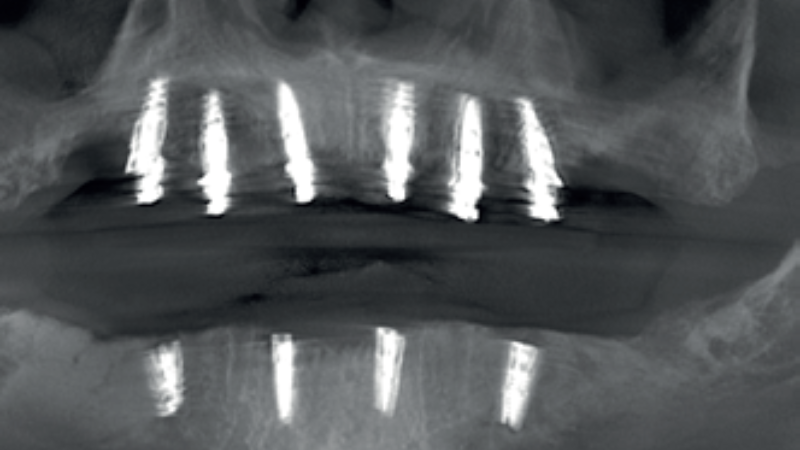

STRESZCZENIE: Celem artykułu jest przedstawienie zastosowania dynamicznej nawigacji implantologicznej na przykładzie systemu X-Guide u pacjenta z bezzębiem. Opisana procedura jest nowoczesna, małoinwazyjna i pozwala na przeprowadzenie interdyscyplinarnego planowania, dzięki czemu pacjent otrzymuje uzupełnienie wsparte na implantach podczas jednej wizyty. Precyzja tymczasowego mostu jest zapewniona przez fotogrametryczne odwzorowanie pozycji implantów, a tymczasowa praca powstaje w technologii druku 3D. W artykule szczegółowo omówiono zarówno etap chirurgiczny, jak i proces laboratoryjny

SUMMARY: The aim of the article is to present the application of dynamic implant navigation using the X-Guide system in a patient with edentulism. The described procedure is modern, minimally invasive, and enables interdisciplinary planning, allowing the patient to receive an implant-supported restoration during a single visit. The precision of the temporary bridge is ensured through photogrammetric mapping of the implant positions, and the temporary restoration [...]